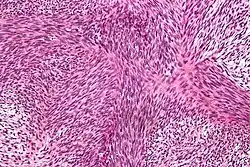

| Micrograph of a tumour with the herringbone pattern as may be seen in fibrosarcoma. H&E stain. | |

The tumor may present different degrees of differentiation: low grade (differentiated), intermediate malignancy and high malignancy (anaplastic). Depending on this differentiation, tumour cells may resemble mature fibroblasts (spindle-shaped), secreting collagen, with rare mitoses. These cells are arranged in short fascicles which split and merge, giving the appearance of "fish bone" known as a herringbone pattern. Poorly differentiated tumors consist in more atypical cells, pleomorphic, giant cells, multinucleated, numerous atypical mitoses and reduced collagen production. Presence of immature blood vessels (sarcomatous vessels lacking endothelial cells) favors the bloodstream metastasizing. There are many tumors in the differential diagnosis, including spindle cell melanoma, spindle cell squamous cell carcinoma, synovial sarcoma, leiomyosarcoma, malignant peripheral nerve sheath tumor and biphenotypic sinonasal sarcoma.